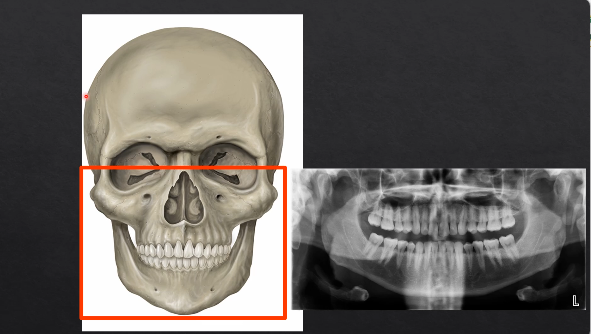

panoramic projections - DPT

technique is a little more specialized

the panoramic radiograph looks different because the specialized technique

patient is positioned in the unit - bite their teeth together on a bite-peg

panoramic DPT cont’d

extraoral because the detector is outside of the patient’s mouth

both the source and the detector will rotate round the patient’s head by 180 degrees

taking X rays at different angles around the patient as it moves round the circumference

as the X rays are produced at the detector they are columnated to an envelope shaped beam - see image where the X rays are produced

then they pass through the patient and are collimated again at the detector at an enveloped shaped area

with a single projection taken at one point of rotation - there is an exposed slit of the detector

with each degree of rotation we are only exposing a a letterbox slit of the detector

as we move points of rotation , more and more of the detector gets exposed → at 180 degrees we fully expose the whole length of the detector

each bit of the detector is being exposed but separately - like a printer - or like a panoramic photo → but this creates some geometric distortion

why is it called a dental PANORAMIC TOMOGRAPH

panoramic - small parts/images stitched together to form the full image

tomograph - refers to the part where we’re taking a slice through the patient’s anatomy

horseshoe shaped slice ??

anything within the green area is referred to as the focal troph - will be formed within the image